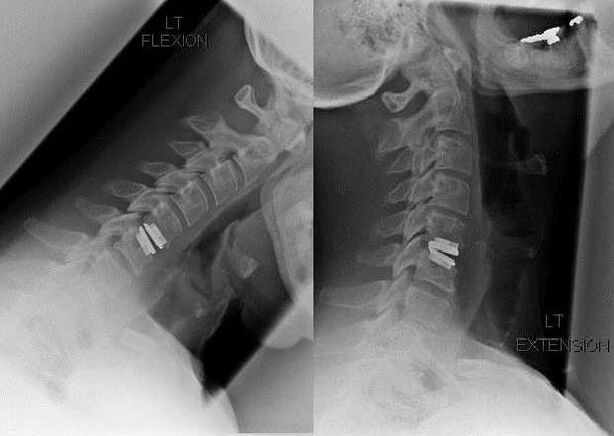

Intervenção cirúrgica

As indicações para intervenção cirúrgica incluem a ineficácia do tratamento conservador, bem como complicações da osteocondrose cervical, por exemplo, mielopatia discogênica, síndrome da artéria vertebral e síndrome radicular. Para descomprimir a medula espinhal, vasos sanguíneos e raízes espinhais, são realizadas as seguintes operações:

- laminectomia;

- laminotomia;

- foraminotomia;

- facetectomia;

- discectomia.

Durante a cirurgia, fragmentos ósseos e ligamentos podem ser excisados e os discos intervertebrais podem ser removidos total ou parcialmente. Para pequenas saliências herniárias, a vaporização a laser do núcleo do disco é frequentemente realizada.

Após a excisão das estruturas vertebrais, a estabilização dos segmentos de movimento da coluna vertebral é frequentemente necessária pela fusão espinhal ou pela instalação de autoenxertos ósseos e dérmicos.